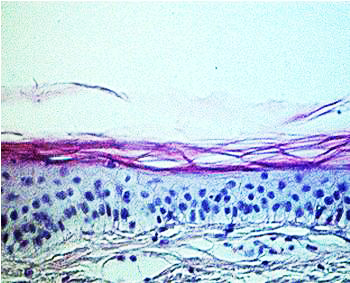

Aged skin can be recognized immediately by the presence of wrinkles, flaccidity and actinic keratosis. A histological section reveals some of the causes of these symptoms of ageing (Fig. 1 a and b).

Fig. 1a: Microscopic sections through the skin of a 21-year-old |

Fig. 1b: Microscopic sections through the skin of a 66-year-old |

Fig. 1

a and b

Microscopic sections through the skin of a 21-year-old and a 66-year-old

In young skin, the

lower part of the skin, the dermis, has a very regular structure. This

regularity is no longer so clear-cut in older skin. The dermis contains

irregular structures and flaws and appears less compact. The next highest

layer, the epidermis, is somewhat thinner in older skin than in younger.

More noticeable than this slight change in the thickness of the epidermis,

however, is the disappearance of the curvature of the epidermal-dermal

interface. In older skin this interface is flat, so that the cohesion

between dermis and epidermis is weaker. Finally, in the upper layer, the

stratum corneum, scarcely any differences can be observed under the microscope.

The main changes are therefore in the deeper layers of the skin, especially